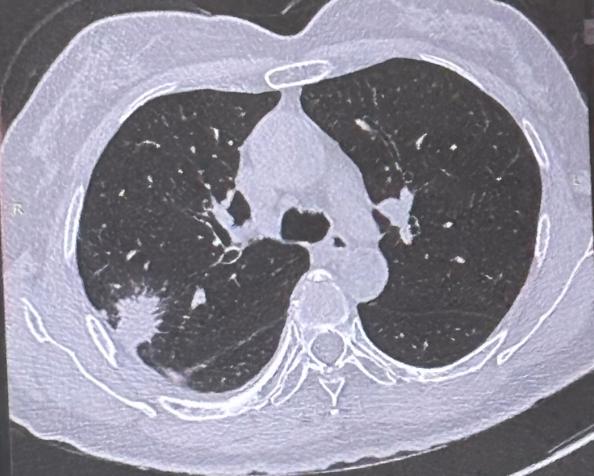

肺腺癌起源于肺泡上皮的腺上皮细胞,这类细胞分布在支气管黏膜下,主要负责分泌黏液,所以肺腺癌大多长在肺的外周部位,离主支气管比较远。

而肺鳞癌起源于气管、支气管的鳞状上皮细胞,这类细胞像鱼鳞、瓦片一样覆盖在气道内壁,因此肺鳞癌通常长在肺部中央区域,靠近主气管。

简单记:腺癌长在外周,鳞癌多在中央。

肺腺癌因为位置偏外周,早期大多没有明显症状,很多人都是体检时偶然发现。等到肿瘤长大,可能会压迫肺组织引起咳嗽,侵犯胸膜出现胸痛、呼吸困难,但早期很少出现咳嗽、咳血。

肺鳞癌就不同了,因为长在中央气道附近,肿瘤早期就会刺激气管,引发持续性咳嗽,剧烈咳嗽还可能震破小血管导致咯血。另外,肿瘤容易堵塞气管,造成分泌物排不出去,不少患者会反复在同一部位发生阻塞性肺炎。